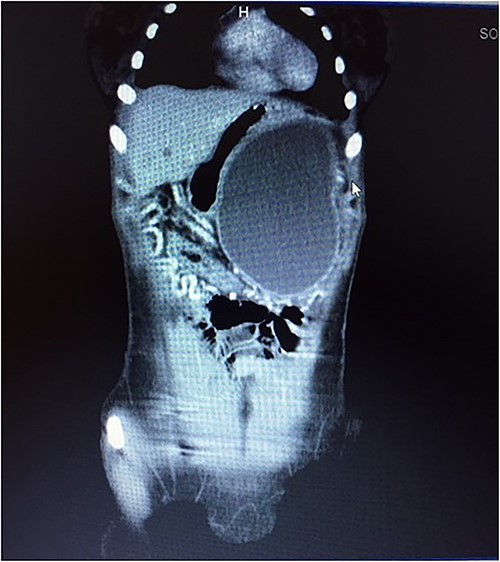

A 21-year-old female collapsed in a market and was taken to a local hospital where she was told that she had a ruptured spleen. She was transfused with two units of whole blood and discharged without surgery. Four weeks later, she noted persistent fullness in her left upper quadrant and presented to our hospital for further evaluation. A contrast CT scan revealed two well-encapsulated, cystic masses in the left upper quadrant, the largest one with small solid components abutting the tail of the pancreas and the smaller one adjacent to the posterior wall of the stomach. She had splenic vein thrombosis, but her portal vein was patent. Numerous portosystemic venous pathways were present, mostly in the gastrosplenic area. The spleen was homogeneous but enlarged with a smooth capsule and normal contour. The liver was normal (Figs. 3 and 4). Her preoperative laboratory studies, including complete blood count, liver function tests, and coagulation studies were normal. A fine-needle aspiration of the anterior mass revealed fresh blood. She was given vaccines against pneumococcus, meningococcus, and haemophilus, anticipating splenectomy would be necessary to resect this mass. At surgery, the splenic artery was ligated at its origin from the celiac axis, which led to an immediate decompression of the peri-splenic and gastric venous collaterals before attempting resection of the mass. The anterior/superior mass was a large, partially organized hematoma, but the inferior mass arose from the tail of the pancreas. A distal pancreatectomy and splenectomy were done en-bloc. The final histopathology revealed a solid pseudopapillary epithelial tumor of the pancreas with negative margins of resection. The patient had an uncomplicated postoperative course and remains asymptomatic.

CT scan showing normal liver and enlarged spleen in close proximity with the mass.